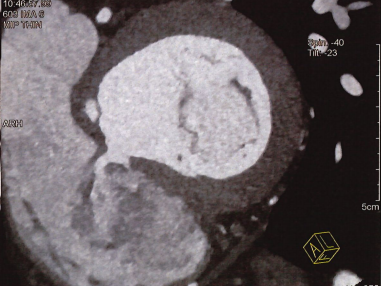

术前CT全方位判断室缺位置、形态及大小